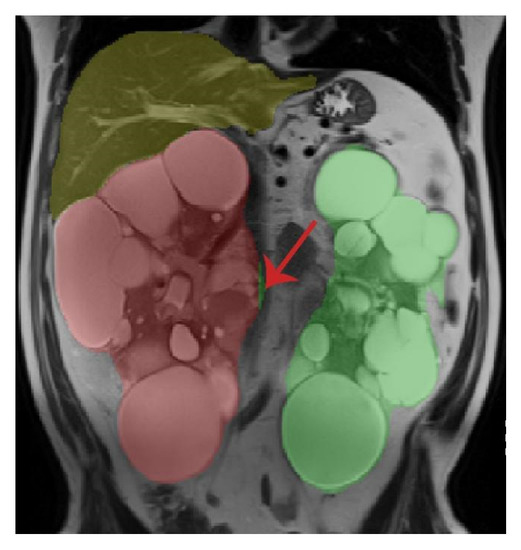

- Riyahi, S.; Dev, H.; Blumenfeld, J.D.; Rennert, H.; Yin, X.; Attari, H.; Barash, I.; Chicos, I.; Bobb, W.; Donahue, S.; et al. Hemorrhagic Cysts and Other MR Biomarkers for Predicting Renal Dysfunction Progression in Autosomal Dominant Polycystic Kidney Disease. J. Magn. Reson. Imaging 2021, 53, 564–576. [Google Scholar] [CrossRef] [PubMed]